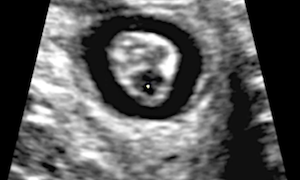

How To Do Gennaio 2021: Ecografia nelle Lacerazioni Ostetriche dello Sfintere Anale

Cari soci, il 2021 si apre con un interessante video "How to do", sul ruolo dell'ecografia nella diagnosi delle lacerazioni ostetriche dello sfintere anale. Grazie a Federica Bellussi! Il video...